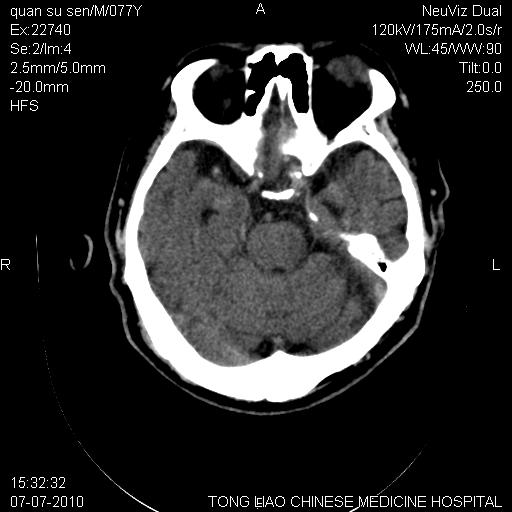

标题: CT27542:小脑病灶

平时经常遇到这样的病例,请问大家,是小脑萎缩还是小脑梗塞?

第一例,头晕、呕吐,复视,左侧肢体麻木

都是单侧小脑半球出现片状低密度灶,可以诊断脑萎缩吗?还是小脑梗塞?

桥---小脑角池 小脑沟增宽 萎缩

ct上显示小脑上沟,就提示小脑萎缩

不是小脑前下动脉梗塞的形态 所以是萎缩

小脑萎缩 ,所致蛛网膜下腔增宽。

ct上显示小脑上沟,就提示小脑萎缩,可以做mri